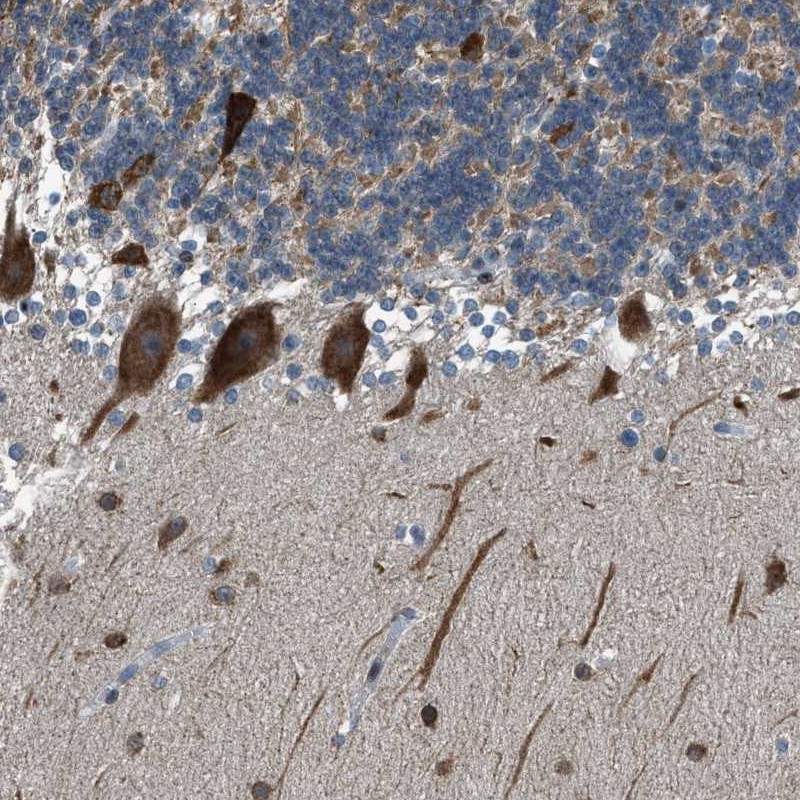

Immunohistochemical staining of human cerebellum shows strong cytoplasmic positivity in Purkinje cells.